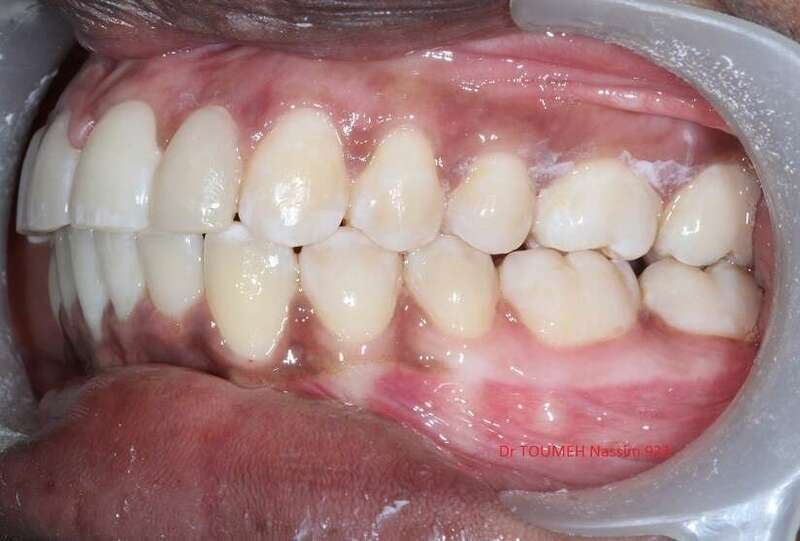

Latérales naines et orthodontie

la forme des dents influence grandement l’esthétique du sourire

La malformation des incisives latérales en est l'illustration

Le traitement consiste à redresser les dents à l'aide d'un appareil orthodontique (Multiattaches) et à redonner une forme normale aux dents malformées.

Dans ce cas présenté des couronnes provisoires en résines ont été posées.

Avant